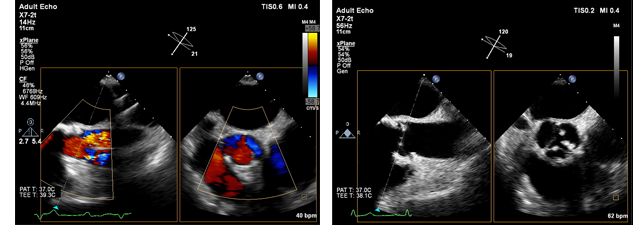

L'imaging Live xPlane crea contemporaneamente due piani di imaging a piena risoluzione, in modo da catturare una quantità di dati clinici doppia nello stesso intervallo di tempo dell'imaging 2D convenzionale.

Durante gli esami cardiaci l'imaging Live xPlane consente di acquisire contemporaneamente due piani dello stesso battito, raccogliendo informazioni di importanza cruciale in tempi rapidi e in modo affidabile.

Imaging xPlane